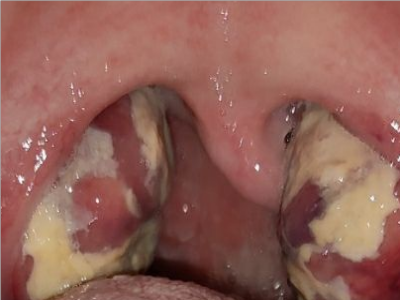

化脓性扁桃体炎扁桃体充血上面覆盖一层厚厚的白色脓苔图

化脓性扁桃体炎咽部两侧扁桃体上附有一层较厚的膜状斑块,颜色为黄白色,边界清晰,大小不等,斑块质地较厚,其下黏膜充血,呈鲜红色。